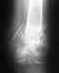

posle pereloma narujney lodyzhki kost' sroslas' no tak kak le4eniye bylo konservativnym kost' polnostyu na mesto ne vstavili, pod uglom vnutr'...hromayu i razrabatyvayu stopu, otrzitsya li tot fakt 4to kost' ne vstala polnostyu na mesto v budushem na amplitude dvijeniy..?

Еще раз. Описание "кость на место не встала, под углом внутрь" не несет информации для конкретного ответа. можно лишь в общем говорить, что хорошее сопоставление лучше, чем плохое. Но что это означает в количественном плане в конкретном случае, без снимка не решить.